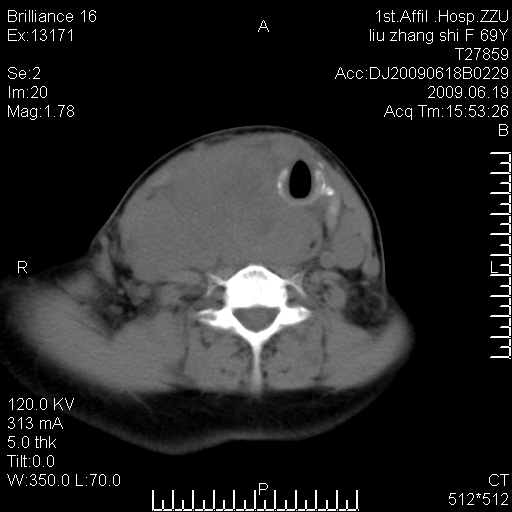

标题: CT26782:女,69岁,颈部占位,3天后公布病理结果。

【病理证实系列】女,69岁,颈部占位,有病理结果,3天后公布。(由于病例时间较久,临床资料不全,请网友见谅)本系列将有几百种常见、少见及罕见病例,均经病理证实。病例资料来自郑州大学第一附属医院。与网友共享,本人有空就发。

甲状腺癌并颈部淋巴结转移。感谢楼主的良苦用心,谢谢。

甲状腺癌并颈部淋巴结转移。

需与鼻咽癌鉴别!

支持甲状腺癌广泛侵及周围结构并颈部淋巴结转移。

鉴别:淋巴瘤、恶性神经源性病变、恶性纤维组织细胞瘤。

病理结果:颈部非霍奇金淋巴瘤。

右侧甲状腺确实有问题